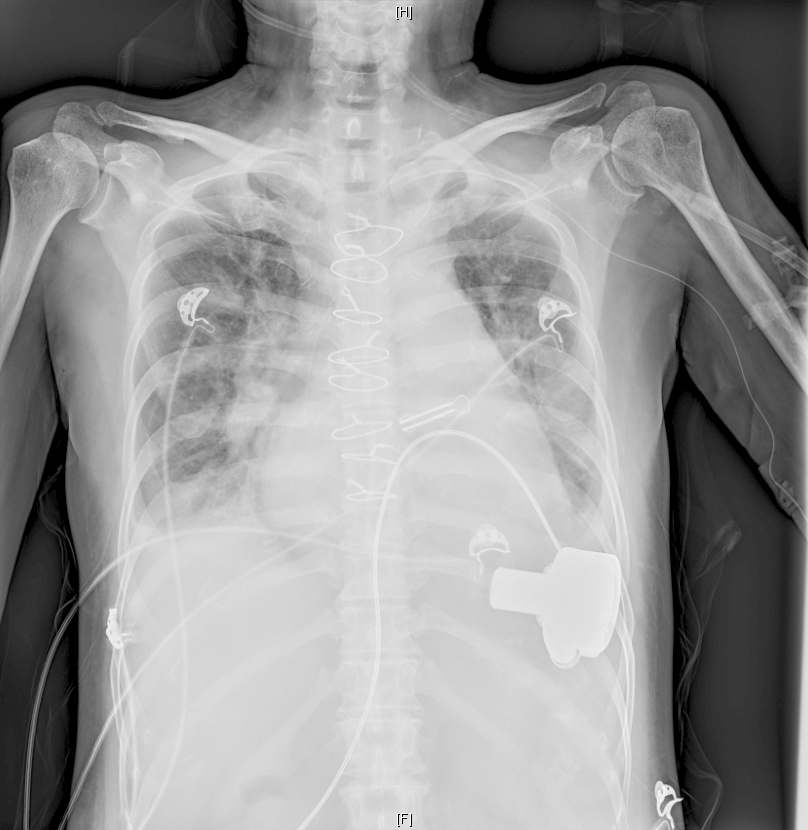

心血管内科崔鸣主任带领CCU团队讨论后果断决定为患者进行植入体外膜肺氧合(ECMO)暂时旷置心脏,规避因为电风暴带来的无休止室速和室颤的循环崩溃,同时通过主动脉内球囊反搏(IABP)减轻心脏负荷,联合气管插管进行深度镇静下辅助呼吸。CCU团队用尽所有利器,病情仍然不可逆地进展到需要器械辅助治疗阶段,意味着“人工心脏”迫在眉睫。ECMO植入的次日,心脏中心组织专家集体讨论为患者植入“人工心脏”的时机。

凌云鹏主任带领团队小心翼翼地将“人工心脏”的泵头缝合至心尖位置,将“人工心脏”另一端与主动脉相连接,开机调试。随着“人工心脏”开始工作,患者逐步脱离了对体外循环、ECMO及IABP的依赖。长达10个小时的手术结束,患者被转运至心脏外科重症监护病房时,天已蒙蒙亮。

为患者成功植入“人工心脏”

手术成功仅仅是万里长征的第一步,心脏外科重症监护团队无数个日夜守护在患者床旁,根据超声影像和血流动力学指标一点一滴地调节着左室辅助装置的流速、流量,静脉用药。面对感染、凝血异常、下肢血栓、坠积性肺炎、急性肾损伤等接二连三的挑战,团队沉着应对,果断采取了气管切开,俯卧位通气等方式,患者转危为安。